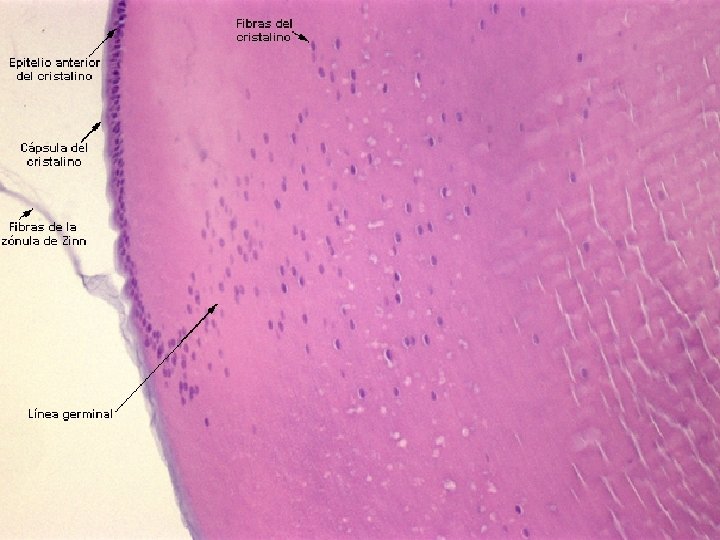

CRISTALINO É uma lente gelatinosa, elástica e convergente que focaliza a luz que entra no olho, formando imagens na retina. A distância focal do cristalino é modificada por movimentos de um anel de músculos, os músculos ciliares, permitindo ajustar a visão para objetos próximos ou distantes. Tem forma de uma lente biconvexa e apresenta grande elasticidade, que diminui com a idade. Constitui-se de: Fibras do cristalino: se apresentam sob a forma de elementos prismáticos finos e longos. Cápsula do cristalino: revestimento acelular homogêneo, hialino , rico e, colágeno do tipo IV e glicoproteínas. Epitélio subcapsular: formado por uma camada única de células epiteliais cubóides. É a partir desse epitélio que se originam as fibras responsáveis pelo aumento gradual do cristalino durante o processo de crescimento do globo ocular.